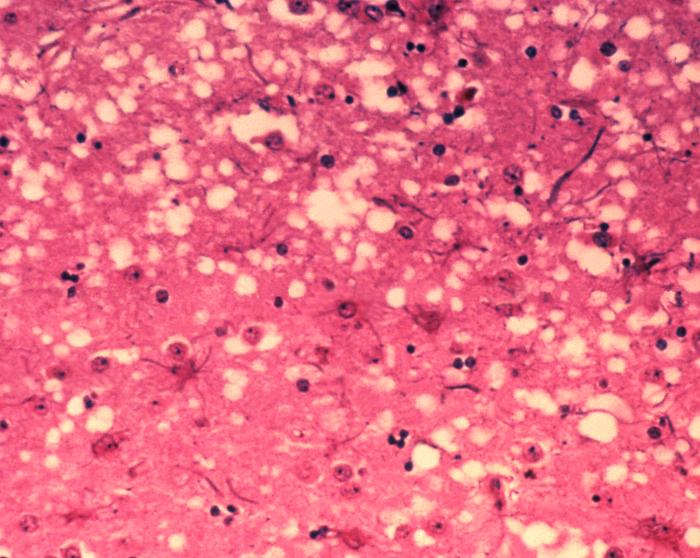

רקמה שנפגעה ממחלת קרויצפלד-יעקב (הפרה המשוגעת) | תמונה: ויקיפדיה

פריונים נמצאים בכל רקמות הגוף, בשרירים, באיברים הפנימיים ואף במוח. הרס התאים המסוכן ביותר לגוף הוא כמובן הרס תאי המוח, שאינם ניתנים לשחזור. אחרי כמה שבועות או כמה חודשים של מחלה, המוח הופך להיות ספוגי, שיש בו יותר חורים מרקמה בריאה, והאדם מת.